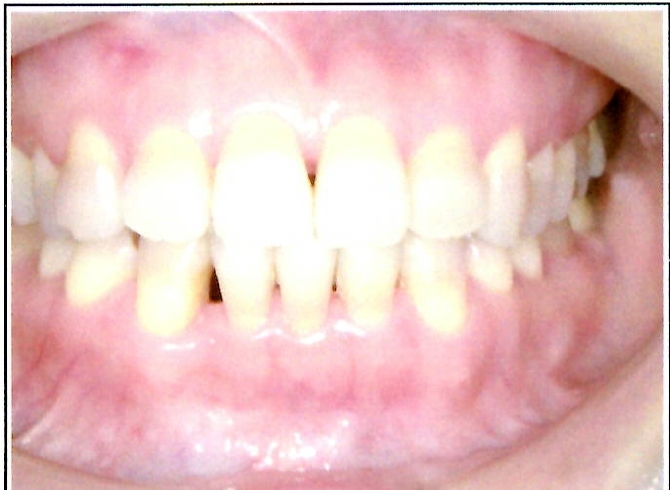

| 主訴・治療前の状態 | 著しい叢生(歯並びのガタガタ)があり、また6歳臼歯(第一大臼歯)が破折していた状態でした。 |

| 治療内容 | 通常の抜歯矯正では第一小臼歯(4番)を抜歯することが多く、その方が治療期間を短縮できますが、小川さんの場合は破折していた6歳臼歯を抜歯し、そのスペースを活用して歯列を整えました。これにより、健康な歯の本数を維持しながら矯正治療を行うことができました。 |

| 治療結果 | 治療前と比較して歯並びが大きく改善し、見た目も大幅に良くなりました。患者様にも大変喜んでいただけた症例です。 |